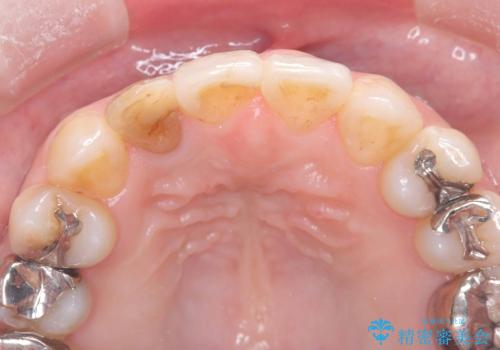

- 「前歯の見た目が気になる」を主訴に来院された患者様です。

失活歯による歯の変色とCR(コンポジットレジン)の劣化による審美不良でした。

オールセラミッククラウンで治療し見た目の改善を行いました。

まず劣化したCRと虫歯を除去した後、仮歯に置き換えました。歯のマージンラインを綺麗に削り光沢が出るまで研磨した後にオールセラミッククラウンの型取りを行っています。